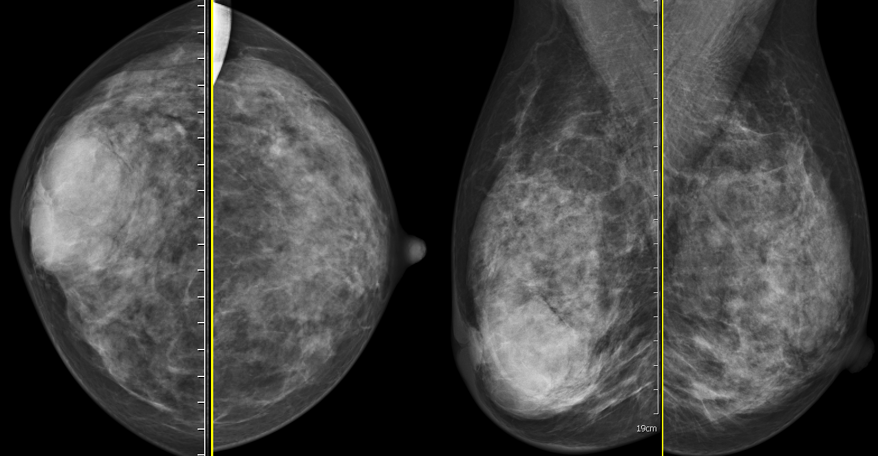

MG/CT: